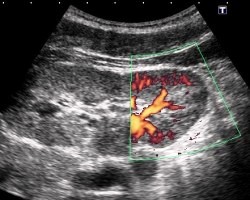

допплер почки - фотоДопплерография сосудов почки – метод ультразвукового исследования, позволяющий оценить состояние кровотока. Данное исследование дает важную дополнительную информацию, которая не может быть получена при обычном УЗИ почек.

В ходе процедуры исследованию подвергаются как сосуды почечной ножки, так и внутритканевой кровоток.